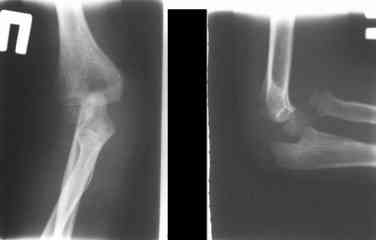

Данную методику применили впервые. После артролиза очевидная нестабильность головки луча. После остеотомии локтевой, вправления и

стабилизации аппарата головка луча при движениях на месте. Первые впечатления- "Либо чудо,либо фокус" (с) :))

1 подвывих головки лучевой кости в положении супинации - через 2 недели после операции- под ЭОП: аппарат разблокирован, повторное вправление головки, стабилизация аппарата.